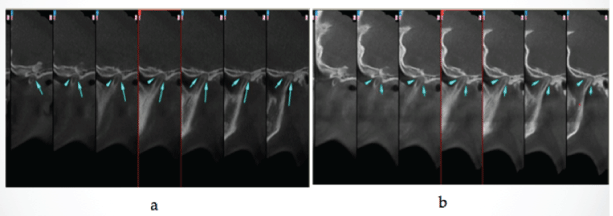

背切迹突出。三维锥形束计算机断层扫描(3D-CBCT) (NewTom 3G, QR, Ferrara, Italy),张口时未观察到前平移,证实了冠突增大的可能性(图5-7)。

图5:矢状位CT显示髁突无移位。a:最大内插位时左髁的矢状位;b:张口位时左髁的矢状位。

图6:矢状位ct显示髁突无平移,a:右髁突最大正中位矢状位;张开大口位右髁矢状位。

下颌活动度低下的鉴别诊断对于指导治疗和提高生活质量是重要的,使用适当的影像学方法对明确诊断是必不可少的。全景x线片和计算机断层扫描证实了诊断。冠突增大的评估可以通过全景x线摄影进行,这是一种简单、经济和有用的检查,可以很好地概述口腔和邻近组织[31]。计算机断层扫描是一种有效的诊断方法。三维锥形束计算机断层扫描(3D-CBCT)提供了冠突及其与邻近结构关系的详细解剖,揭示了颧骨中嵌塞发生的位置[3,32]。3D-CBCT对冠状突增生[33]的诊断和手术计划有重要意义。在这些病例中,通过全景摄影和3D-CBCT成像技术证实了冠状突增生的临床诊断。双侧髁突移位缺失、冠突细长尖、髁突发育不全、髁突表面光滑,与既往研究结果相似。